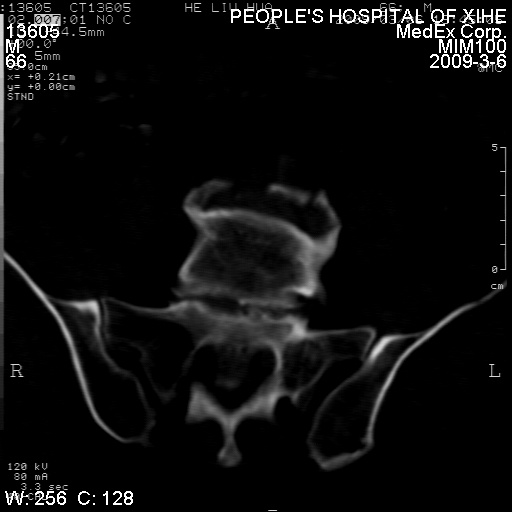

标题: CT18522:男,66岁。考虑结核有错吗 [打印本页]

标题: CT18522:男,66岁。考虑结核有错吗

x线片示:骶骨密度增高。

考虑----腰椎骶化-----退变-----椎管狭窄

退行性变,椎体滑脱

腰椎滑脱并有退变

退行性变,椎体滑脱。建议同椎体平行进一步扫描。